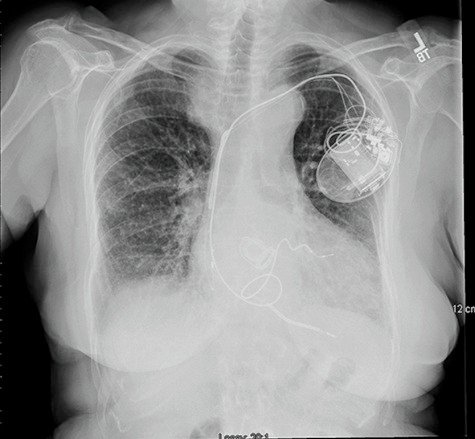

I am 49 … not out, how about you TAVI ?

Posted in Uncategorized, tagged prosthetic aortic valve, starr edwards valve, tavi valve on August 1, 2023|

This post was written after coming across a case report Oxford medical case report.

What is the life of a prosthetic Aortic valve?

The standard answer needs to be, mechanical valves can last up to 25 years or more. But, we are in a techno-conflict era. Instead of working on the longevity of the valve, ( with concerns for long-term OAC ) we fell for the biological valves. Curiously, this has made the durability of the valve, a less relevant discussion in many centers. We get excited when some company brings out a long-lasting bio-prosthetic valve that can live up to a maximum of 15 years.

Now, the biological valve comes in a new avatar ie TAVI, in a big way. Soon, we may celebrate an event free 10 years after TAVI. Going percutaneous is transformative. But at what cost? Fusion of metallurgy, chemistry, and pharmacology should make it possible for in-vivo metal valves to be safe for 75 years of human life span. The irony is we almost had one, One valve’s longevity was consistently exceeding the patient’s life span,(at least as far as we observed in the Rheumatic heart disease) This has been the star of all valves. We know what happened to that valve.

Final message

Most SE valves are implanted in the mitral position. Starr-Edward in an Aortic position working for 50 years is a big proof of reality. Of course, we can’t extrapolate with a single case report. We have stopped the production of these valves. So, there is no way to test it either. Anyway, cardiologists, cardiac surgeons, and finally the generation X, TAVI Innovators have something to learn from this case report. Forget Starr-Edwards, It looks like, there are some invisible forces that work against mechanical valves in recent times, which may not be good for our patients as of now. (There is something interesting related to this in Ref 2)

Future directions: Past need not be past

Nothing is impossible for our hyper-talented scientists, except probably in the “faculty of looking back” the past-Innovations (falsely labeled as obsolete) and bringing them again to optimal usage. If cardiologists feel surgical AVR injures their interventional pride, how about a percutaneous cage delivered at the root of the aorta, after ablating native leaflets, followed by an inflatable silicone ball?

Reference

A current 2023, opinion from the renowned Dr. Catherine Otto on this Mechanical vs biological valve , Indications, current usage pattern, the cut-off age, etc